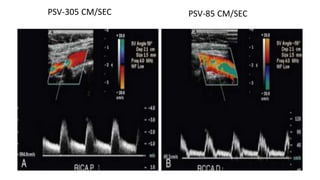

• PSV < 125 cm/sec and PSVR < 2.0 suggest a stenosis < 50%

• PSV between 125 and 230 cm/sec and PSVR between 2.0 and 4.0 are most

consistent with a stenosis of 50% to 69%

• PSV > 230 cm/sec, PSVR > 4.0, and EDV > 100 cm/sec indicate a stenosis of

≥70% to 96%

PSV-305 CM/SEC PSV-85 CM/SEC

The SRU conveneda multidisciplinary panel of experts, including both radiologists and vascular surgeons, to develop a consensus for grading of ICA stenoses by Doppler ultrasonography. The published recommendations of this consensus conference are as follows: • PSV < 125 cm/sec and PSVR < 2.0 suggest a stenosis < 50% • PSV between 125 and 230 cm/sec and PSVR between 2.0 and 4.0 are most consistent with a stenosis of 50% to 69% • PSV > 230 cm/sec, PSVR > 4.0, and EDV > 100 cm/sec indicate a stenosis of ≥70% to 96%